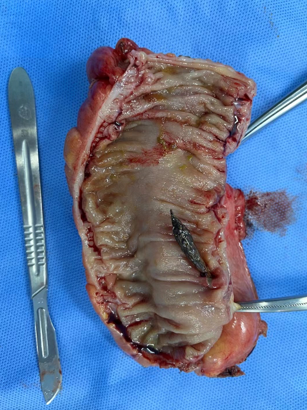

老太太被送入手术室,在急诊全麻下行腹腔镜剖腹探查手术,大肠外科李军主任医师通过精湛的技术,找到了导致肠穿孔的罪魁祸首——一颗小小的枣核。

手术中,李主任发现穿孔位于乙状结肠下段,距离直肠肛门很近,在穿孔部位以上部分节段肠管已经出现缺血坏死,穿孔处周围有积液,并有腹膜炎症表现。手术进行约2小时,切除了穿孔及缺血段肠管,并放置了两根腹腔引流管引流炎症性腹腔积液,术后安返ICU,转危为安。